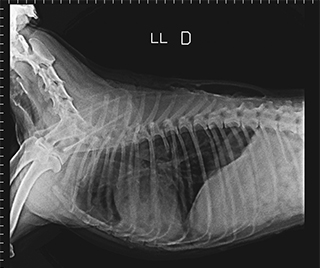

Radiologia Digital Direta / Digital Radiography

As radiografias geradas digitalmente podem ser transmitidas para iPad Apple®, notebooks e smartphones.

iPad com tela Retina Apple® possibilita a visualização das imagens com maior qualidade diagnóstica.